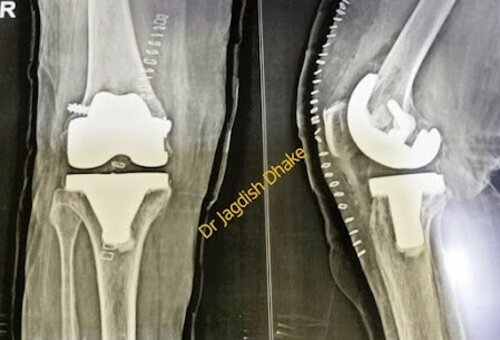

Bilateral Total Knee Replacement | Dr. Jagdish Dhake

Dr. Jagdish Dhake - Orthopedic Surgeon in Pune handles a case of patient by undergoes Bilateral Total Knee Replacement. Now the patient is able to wal...